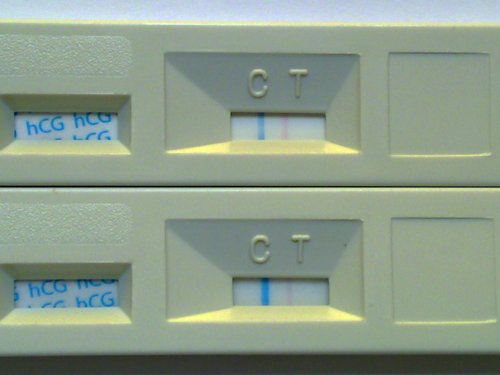

betty: mai tesztre nagyon kiváncsi vagyok, szerintem sem a szurit láthattad a tegnapi csíkon